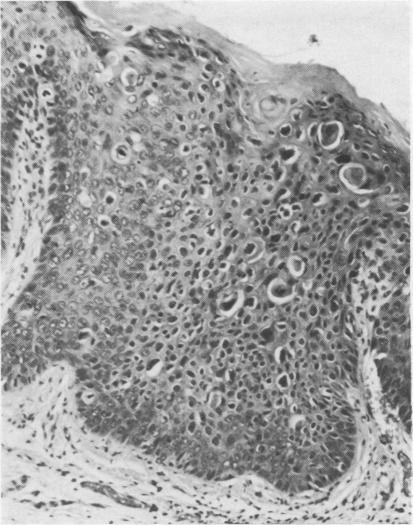

The pathological, cytological, and clinical features of vulvar intraepithelial neoplasia (VIN) are described. The rate of progression of VIN III to an invasive carcinoma is very low and spontaneous regression can occur. These features prevent the drawing of a direct analogy between vulvar and cervical intraepithelial neoplasia. The concept of microinvasive carcinoma of the vulva is discussed, and it is concluded that no satisfactory definition of this entity has been achieved.

本文描述了外阴上皮内瘤变(VIN)的病理、细胞学及临床特征。VIN III进展为浸润性癌的发生率很低,且可发生自发消退。这些特征使得外阴上皮内瘤变与宫颈上皮内瘤变无法直接进行类比。文中对外阴微浸润癌的概念进行了讨论,得出的结论是尚未对该实体达成令人满意的定义。